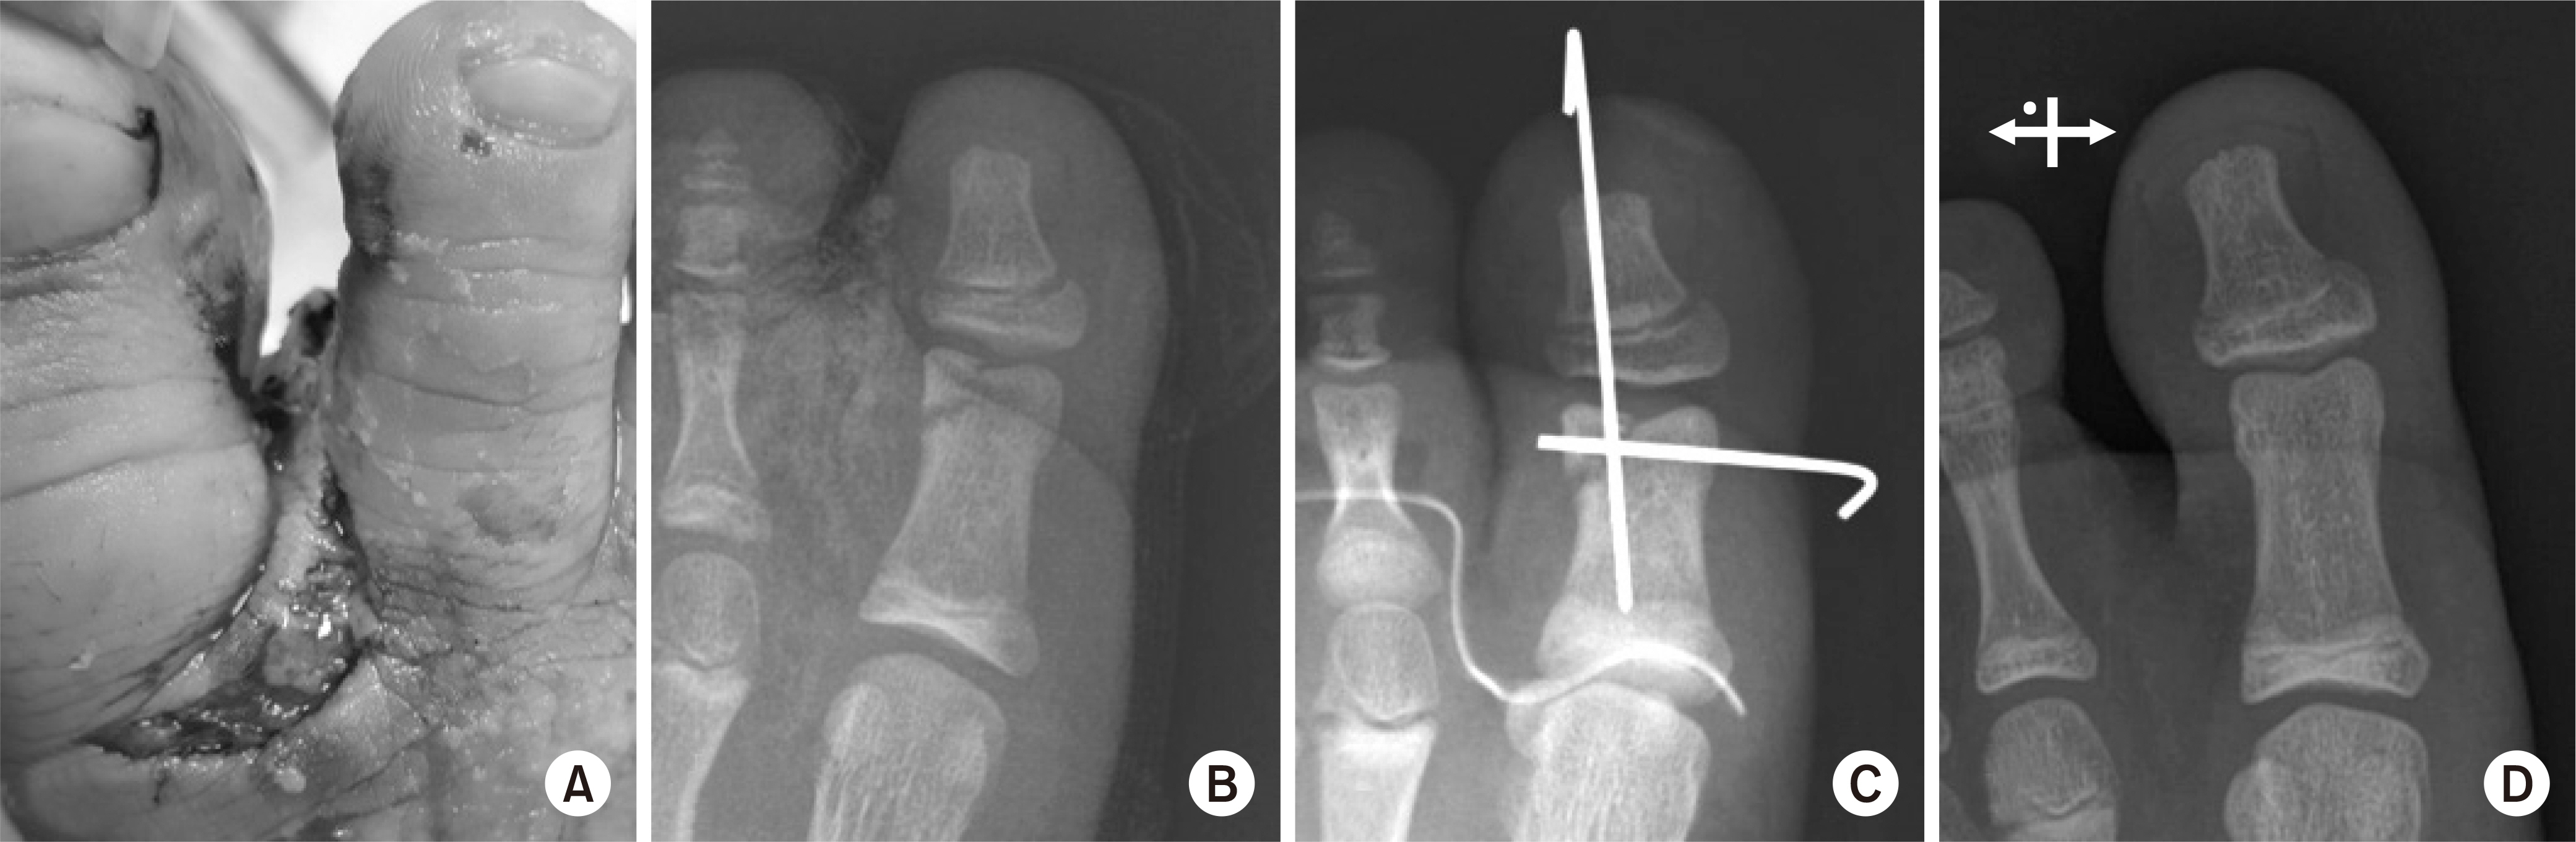

Fig. 7.

(A, B) A case of acute fracture with forefoot laceration. (C) Stable fixation was achieved using two K-wires. (D) Follow-up X-ray at 2 years postoperatively.